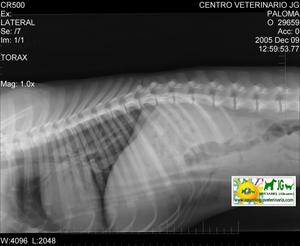

![]() por Juan M. Griñán. Veterinario ![]() comparativa entre una mielografía (mostrando la aguja) y una resonancia magnética, secuencia SE T1w (mostrando donde está el saco dural, sitio para la inyección del contraste). Nótese la extravasación del contraste yodado en la mielografía. | |||||||||